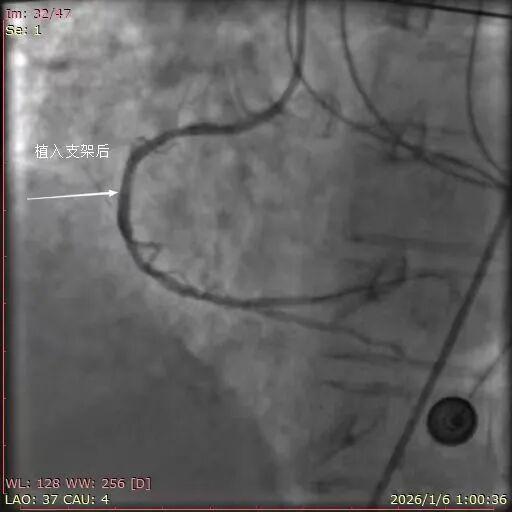

1月5日 ,23点00分,患者高某,女,71岁,突发胸闷憋气6小时就诊于平度市第三人民医院胸痛中心,值班医生迅速为患者完善床旁心电图检查,检查结果提示“窦性心动过缓、急性下壁心肌梗死、III度房室传导阻滞”。测血压86/60mmHg,合并心源性休克,患者病情危重,立即抢救。建立静脉通路,快速补液,应用血管活性药物升压等。患者平日身体一般状况较差,目前病情危重,王建东副主任医师与患者家属进行了充分沟通,并建议行急诊冠脉介入治疗。患者家属对患者病情充分知情,经充分考虑后同意并签字。随后,患者被送入导管室。术中造影结果显示:右冠状动脉近段完全闭塞,TIMI血流0级。

与患者家属沟通并获得同意后,医护人员迅速为患者介入诊疗,将6F SAL.75指引导管送至RCA开口处,将SION导引导丝送至RCA病变远端,以2.0×15mm 球囊预扩张(10ATM/5S)后,复查造影,可见血栓影,送入抽吸导管抽吸血栓,抽出红色长条血栓,复查造影远段无复流,冠脉内给予注射用重组人TNK组织型纤溶酶原激活剂2mg冠脉溶栓,复查造影TIMI血流3级,于病变处植入3.0×18mm药物洗脱支架(16ATM/5S)一枚,无明显残余狭窄,TIMI血流3级。术中应用硫酸阿托品注射液、重酒石酸去甲肾上腺素注射液、盐酸多巴胺注射液等抢救药物。

介入干预后,患者胸痛、胸闷症状明显减轻,术后收住CCU病区继续治疗。住院期间患者经历了心源性休克,急性心力衰竭,肺部感染,肝功能受损等重重难关,病情逐渐平稳,转心内科普通病区,住院8天,康复出院。